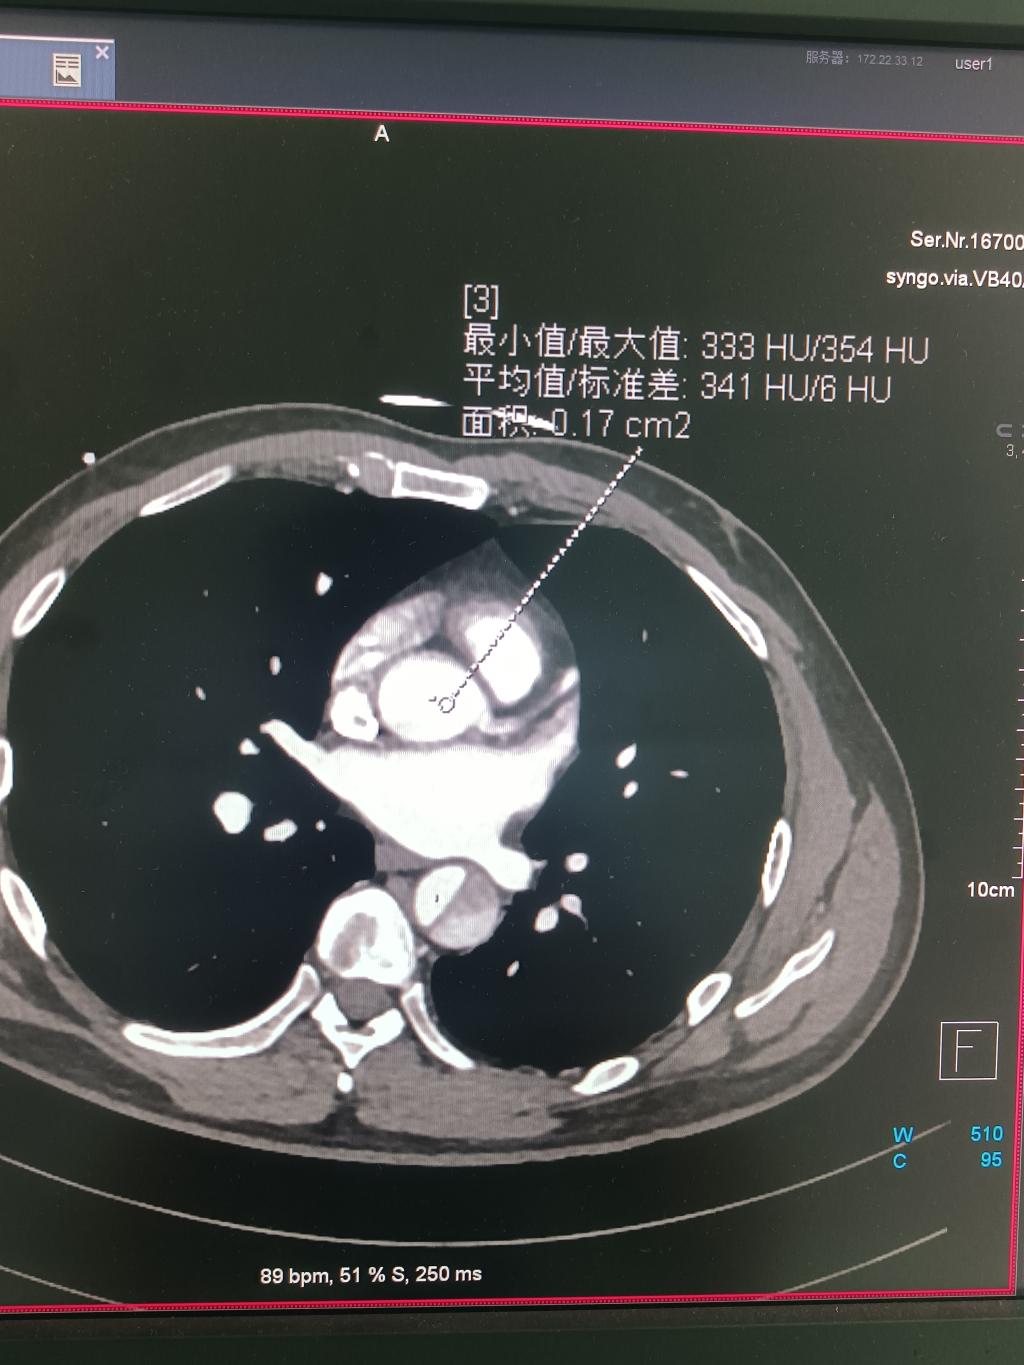

冠状动脉主干及分支显示较好,胸、腹主动脉显示较好,肺动脉主干及分支显示较好。

主动脉平均CT值为341HU

肺动脉主干平均CT值为308HU,左侧冠状动脉主干平均CT值为308HU。根据全国专家共识:血管CT值浓度超过300HU即可诊断。